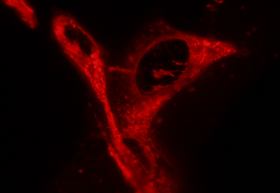

Estradiol Glow is the ovarian steroid hormone 17-β-Estradiol labeled with a novel low molecular weight orange/red fluorophore, thus retaining its chemical properties and its biological activity. This allows for a wide range of applications including

- analysis of in vivo and in vitro steroid uptake in real time

- monitoring of intracellular and subcellular steroid transport

Figure 1: 1 µm section of 3T3 cells incubated with Estradiol Glow shows internalization and subcellualar compartimentalization.